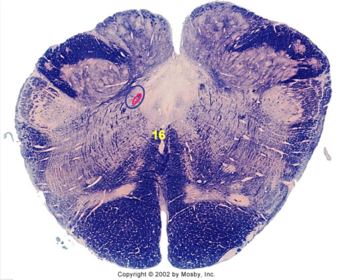

| Solitary nucleus | |

| ALS | |

| Medial lemniscus | |

| Medial longitudinal fasciculus | |

| Spinal tract of V | |

| Spinal nucleus of V | |

| Medial vestibular nucleus | |

| Inferior vestibular nucleus | |

| Dorsal cochlear nucleus | |

| Ventral cochlear nucleus | |

| Inferior olivary complex | |

| Inferior cerebellar peduncle | |

| CN IX | |

| Anterior spinocerebellar tract | |

| Central tegmental tract | |

| Olivary internal arcuate fibers | |

| Solitary tract | |

| Abducens root fibers | |

| Longitudinal pontine fibers (corticospinal tract) | |

| Transverse pontine fibers (dark fibers) | |

| Pontine nuclei (pale) | |